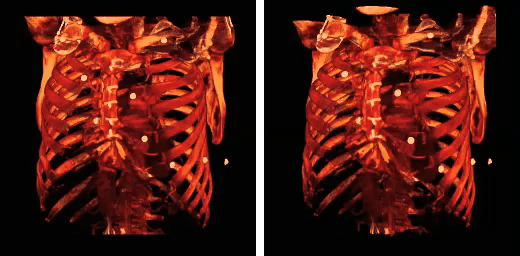

Additional images